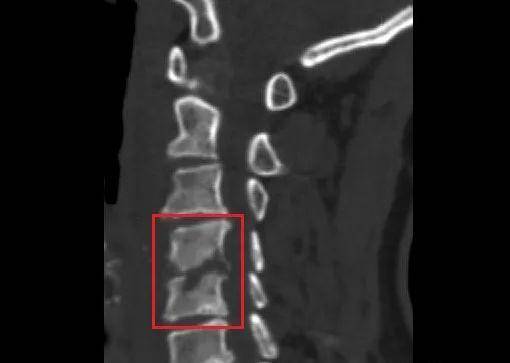

在医院疼痛科 , 医生给王女士做了影像检查 , 发现她的颈椎周围形有大量脓肿 , C4、C5椎体的骨质已经被吞噬得“面目全非” ,出现了几处明显的缺口 。

如图 , 红圈部分↓↓↓

文章图片